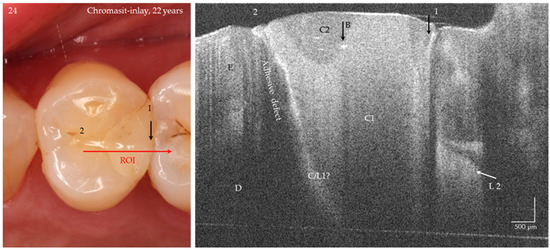

Figure 16.

Chromasit® inlay on tooth 24 after 22 years of clinical service. The OCT-B scan of the tooth-restoration interface shows an extended marginal and deep interfacial gap (position 2, bright signal line) without signs of secondary caries. At and beneath the enamel-dentin junction, a bright zone indicates a carious lesion at the tooth-composite contact zone or a cracked zone in the bonding composite (C/L 1?). Gap 1 is the gap between the teeth (short bright signal line). The restoration materials C1 (dentin color) and C2 (enamel color) contain single bubbles (B). A proximal lesion L 2 on tooth 25 mesial is visible, which could also be confirmed tactile (ICDAS, code 3) after OCT imaging (verification). Composite (C), enamel (E), dentin (D). Refractive index n = 1.0 (see Figure 4).